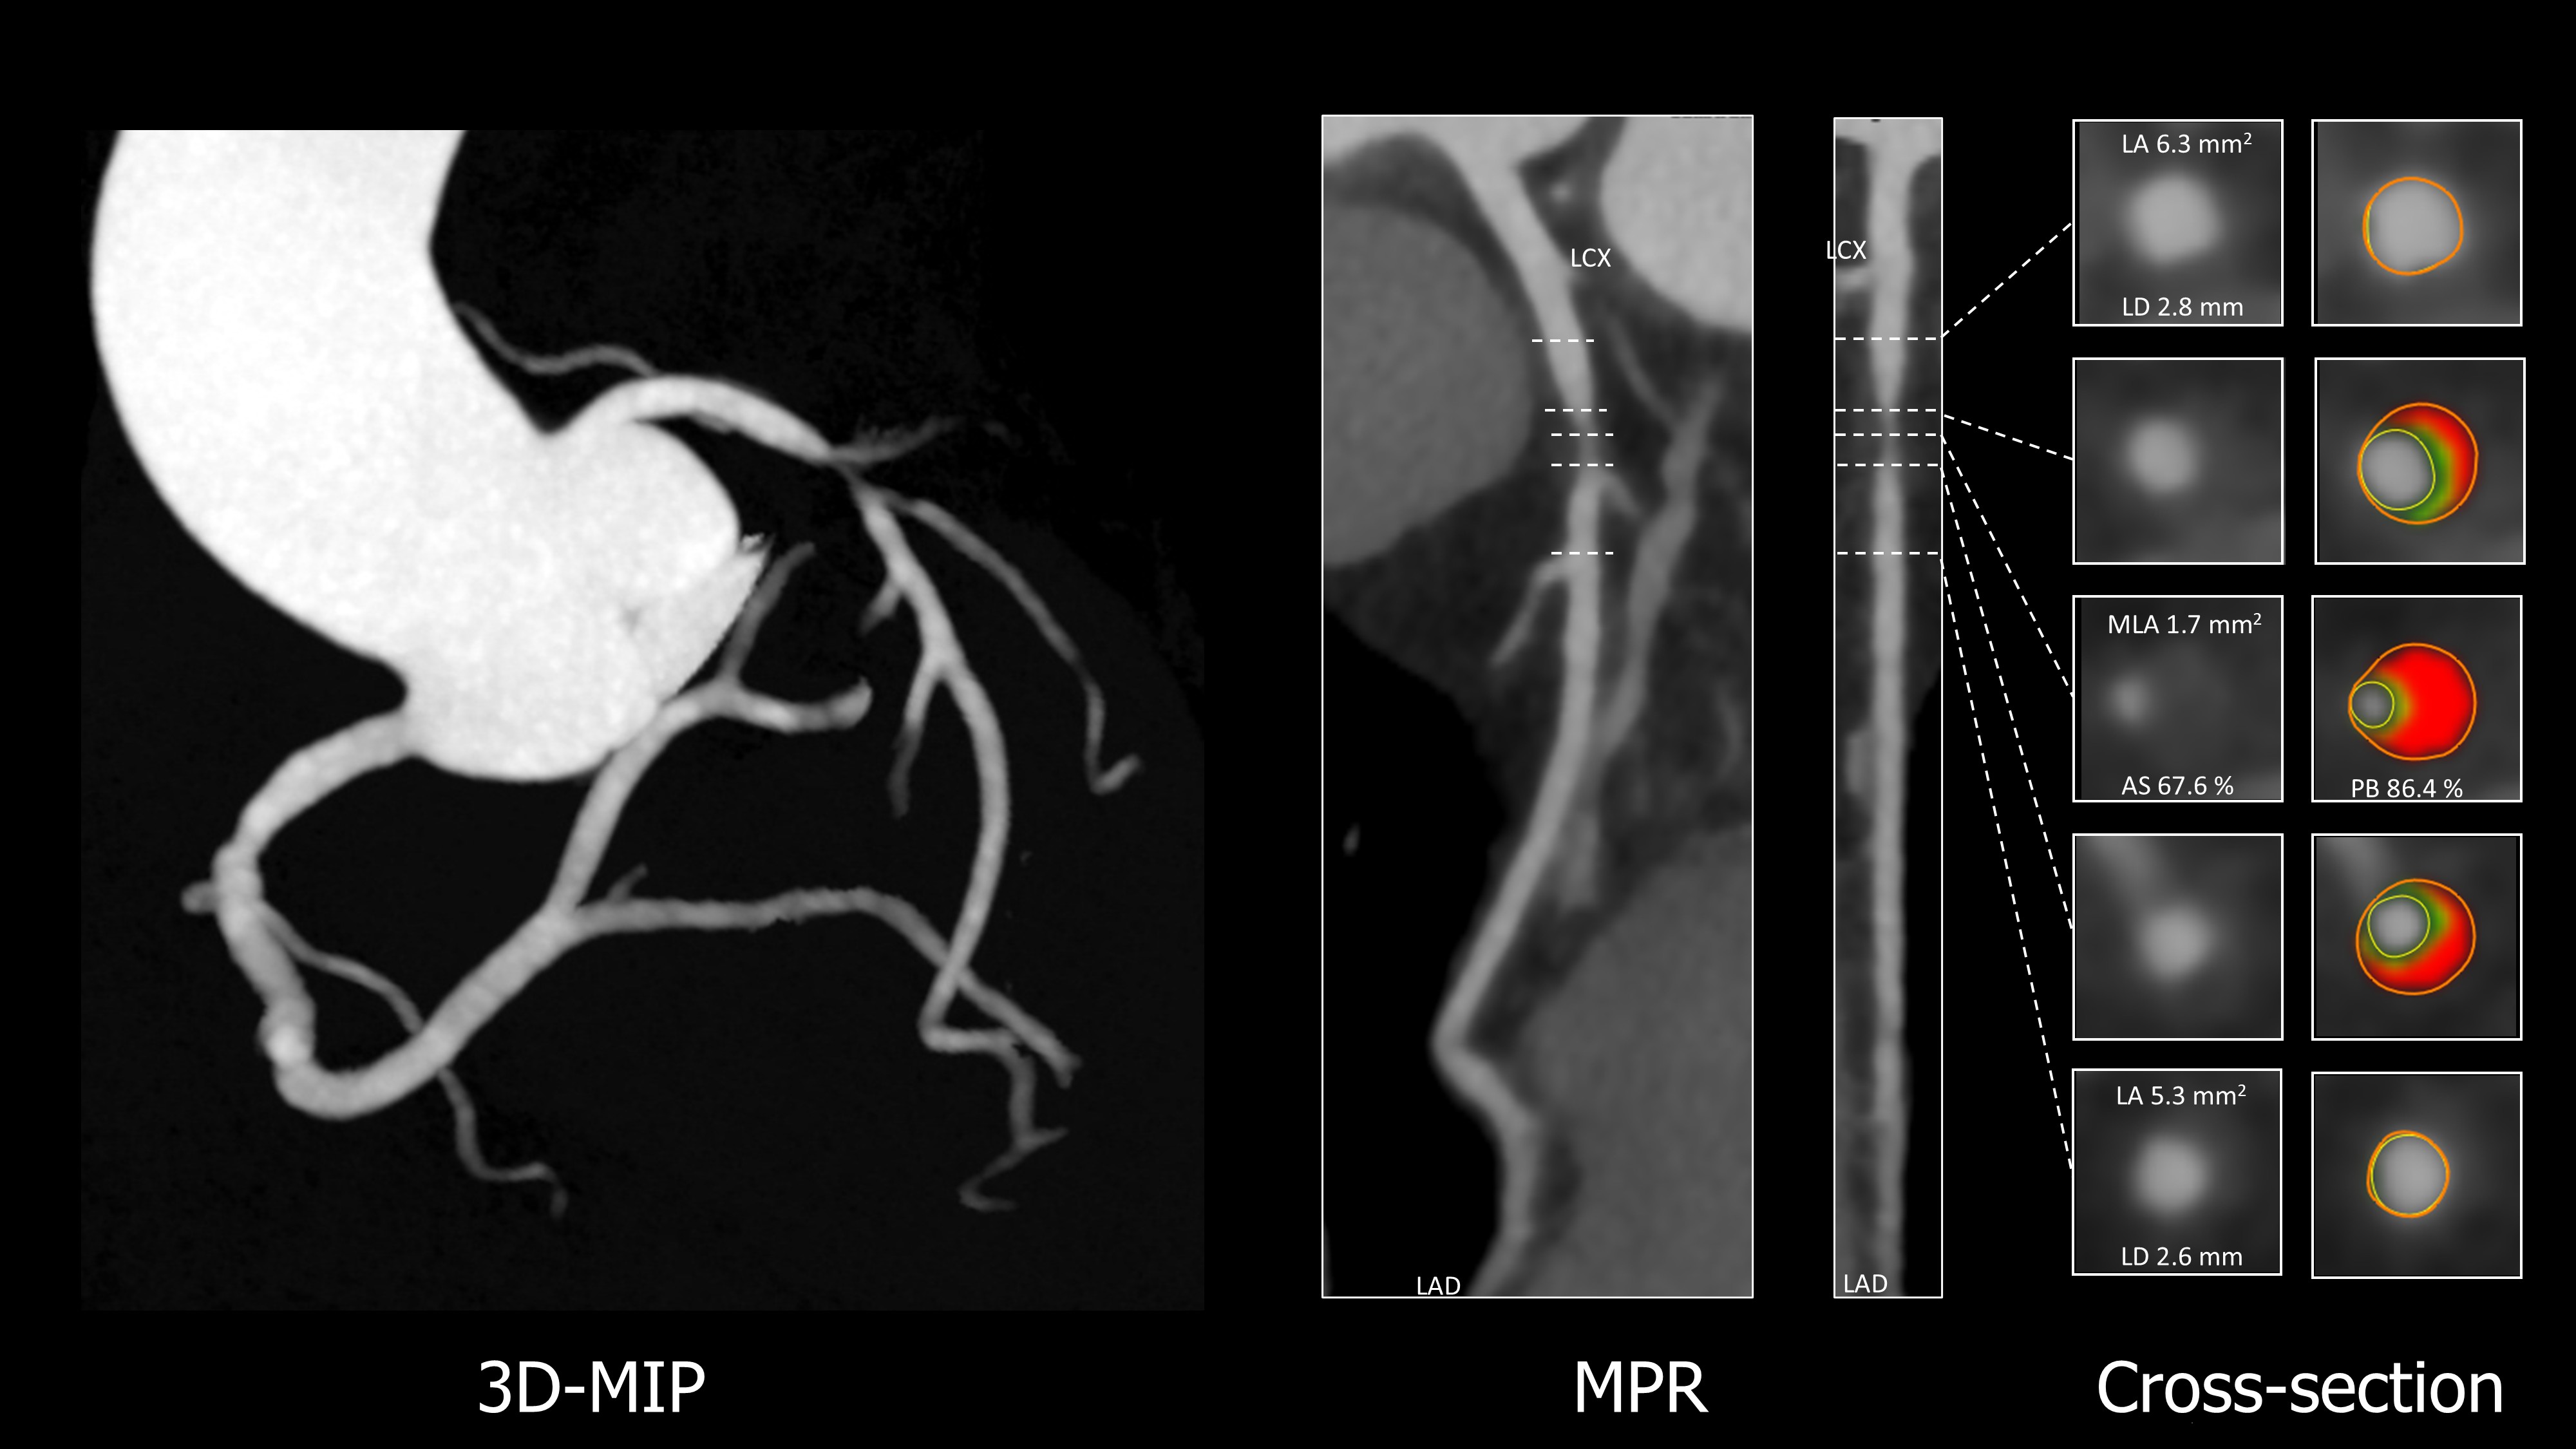

Coronary CT angiography (CCTA) demonstrated significant stenosis in the proximal left anterior descending artery (LAD). CT-derived fractional flow reserve (FFRCT) showed ischemia (0.68). CT analysis guided stent sizing with 23mm. The lesion was predominantly lipid-rich without calcification, requiring no modification. Virtual PCI using the FFRCT Planner predicted post-PCI FFRCT of 0.92.